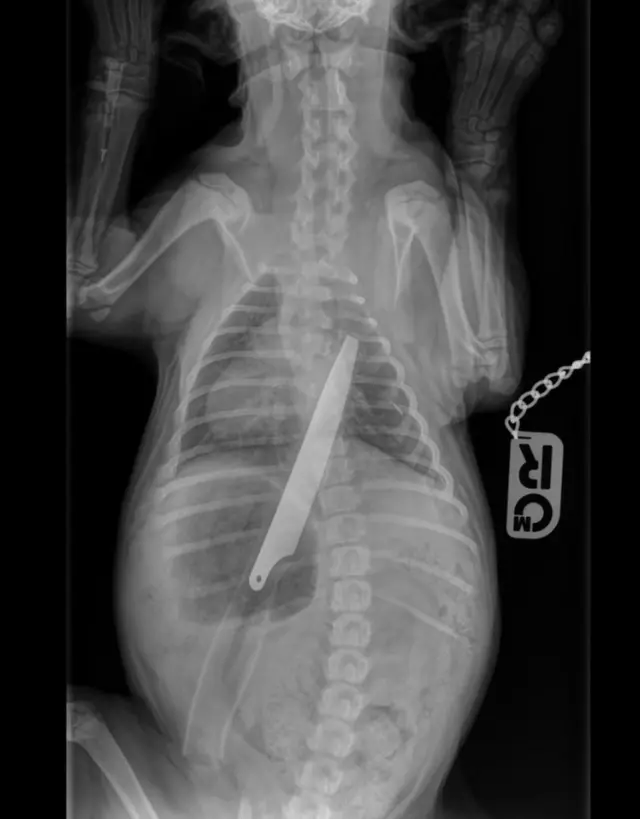

Mbwa ambaye alimeza kisu cha urefu wa sentimita 20 anapata nafuu baada ya kufanyiwa upasuaji.

Mbwa huyo wa umri wa wiki 12 kwa jina Macie, alikimbizwa kwa daktari wa mifugo kwa huduma ya dharura baada ya kuanza kukohoa.

Mwenye mbwa huyo anasema alidhani kuwa alikuwa amemeza kifaa cha kuchezea cha watoto, lakini X ray baadaye ilionyesha picha ya kisu kikuwa tumboni.

Daktari ambaye amekuwa akimtunza mbwa huyo tangu afanyiwe upasuaji anasema ana habati sana kuwa hai.

Siku moja baada ya kufanyiwa upusuaji alionekana mchangamfu. Mbwa huyo amekuwa akirudishwa kwa daktari kufanyiwa ukaguzi kwa muda wa wiki mbili na sasa anaendelea kupata nafuu.